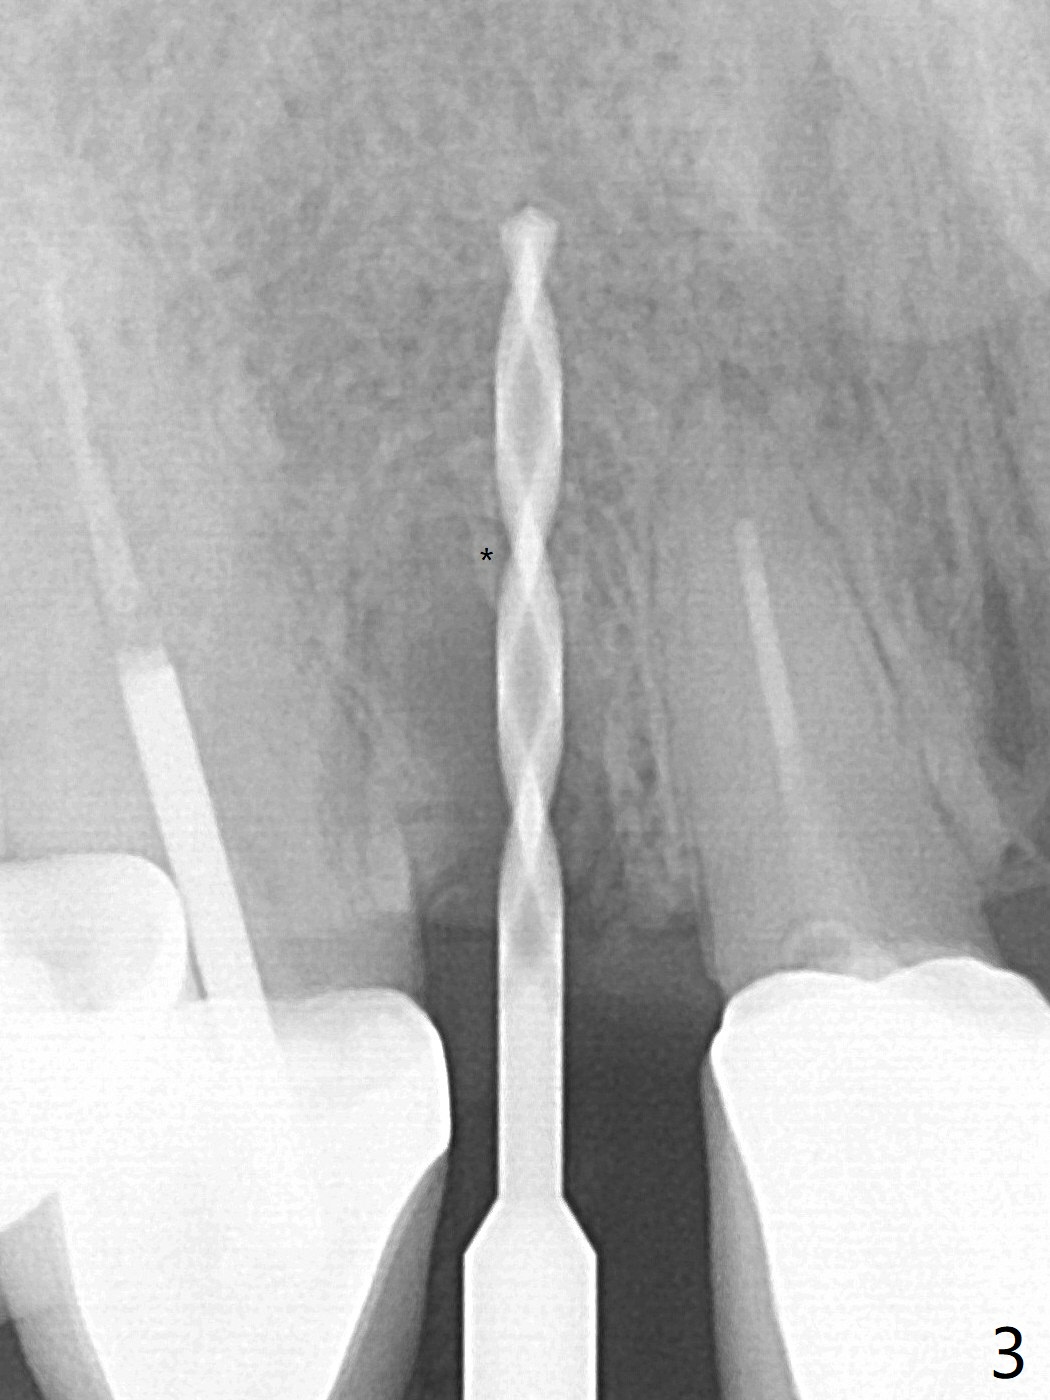

Because of the long crowns of the neighboring teeth, it is difficult to remove the apical portion of the root, including gutta percha with surgical handpiece (Fig.3 * (1.2 mm drill for 12 mm)) for socket shield. To avoid the perspective implant touching socket shield, initial osteotomy is palatal. When a 2 mm drill is being used, the coronal end of the palatal plate starts to perforate. A 2.5x14 mm 1-piece implant is placed with 30 Ncm (Fig.4). The teeth #8 and 9 fracture (an implant is placed at #8 and bone graft at #9), while the implant at #7 is osteointegrating (Fig.7). In fact the shield is exposed without symptom.